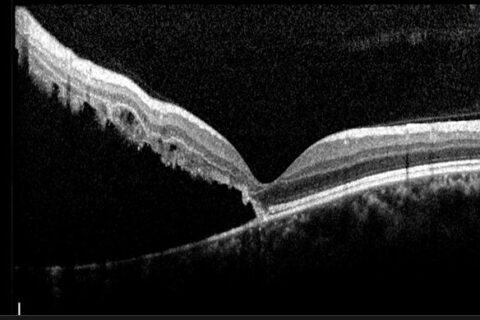

Μερικού πάχους οπές ωχράς κηλίδας

Σε αντίθεση με τις ολικού πάχους οπές της ωχράς, όπου η παθοφυσιολογία, η διαγνωστική προσέγγιση και οι ενδείξεις χειρουργικής παρέμβασης είναι εν πολλοίς ξεκάθαρες και κοινώς αποδεκτές, οι οπές μερικού πάχους παρουσιάζουν μεγαλύτερη ετερογένεια ως προς τους μηχανισμούς και τα χαρακτηριστικά τους, ενώ τα διαγνωστικά τους κριτήρια, η κατηγοριοποίηση και ο σχεδιασμός της βέλτιστης αντιμετώπισης…